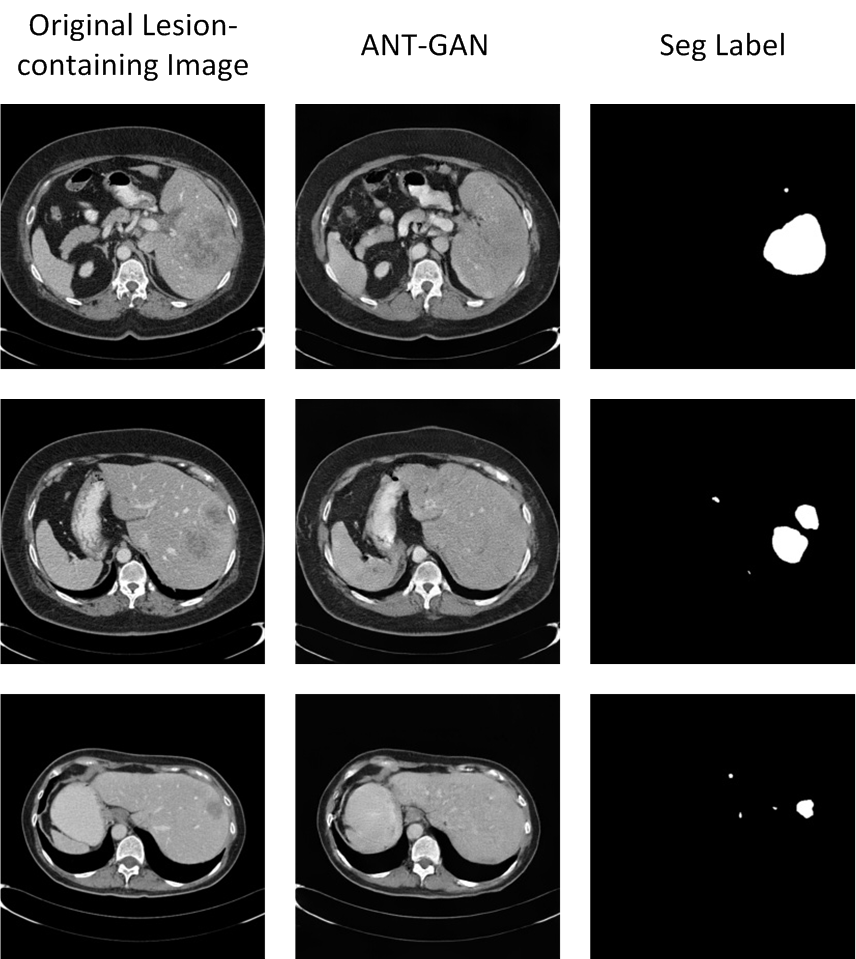

IV-E Results on the LiTS Challenge dataset.

We also implement ANT-GAN on the LiTS dataset and show some qualitative results in Figure 11. We observe that the lesions in the liver CT data appears with much lower contrast than in the brain MRI data. While our model can detect and modify the abnormal regions successfully, we note that there are more deformations than with the BratS18 dataset, which is a result of this more difficult task.

Refer to caption

Figure 11: Experimental results on the Liver CT data (LiTS).